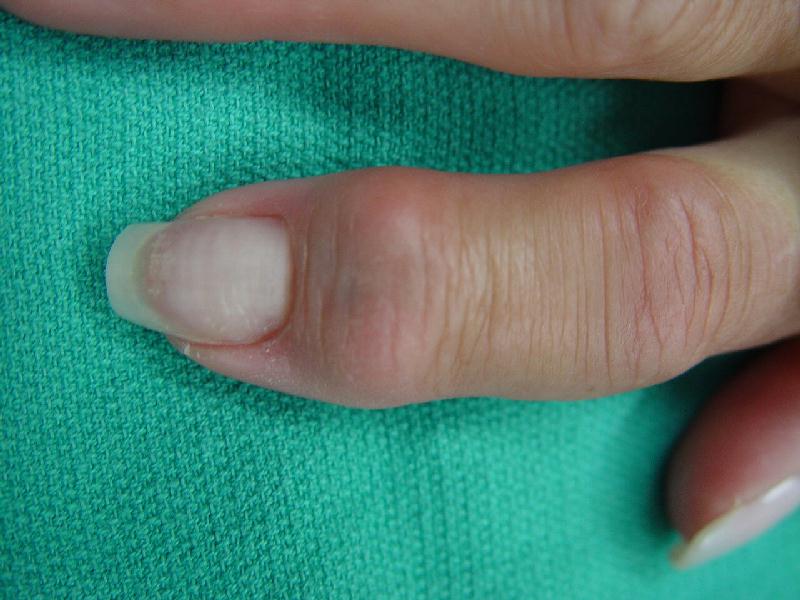

Dorsolateral eponychial splitting incision. The black debris represents foreign body pencil lead debris from a childhood injury.

The implant in place. The approach was similar to the bayonette exposure  demonstrated in  this case.